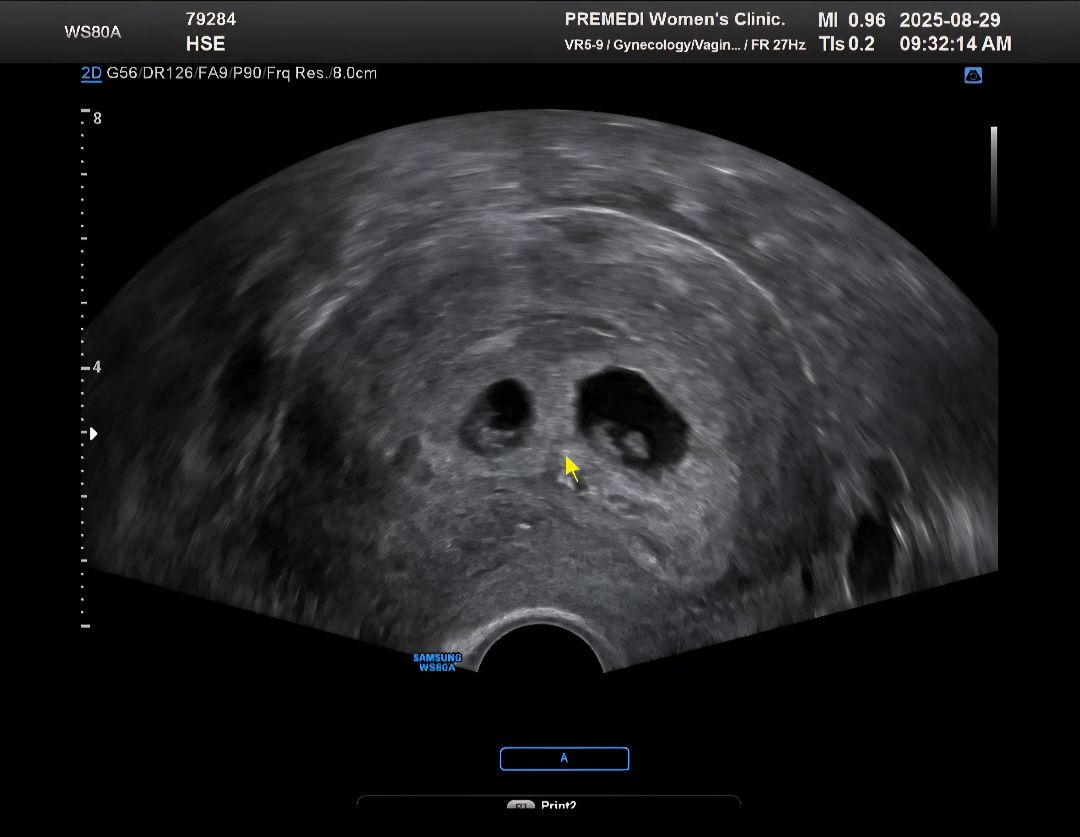

첫찌도 시험관으로 하고 둘째 안생겨서 동결배아이식했는데 웬걸ㅠㅠ 쌍둥이가 생겨버렸어요~~ 이제 7주0일차! 둘다 우렁찬 심소듣고 왔어 갑자기 애셋맘이 되버리겠어요👀 아기집도 두개 아기도 둘 있는게 너무 신기하고 기분이 몽글몽글💞